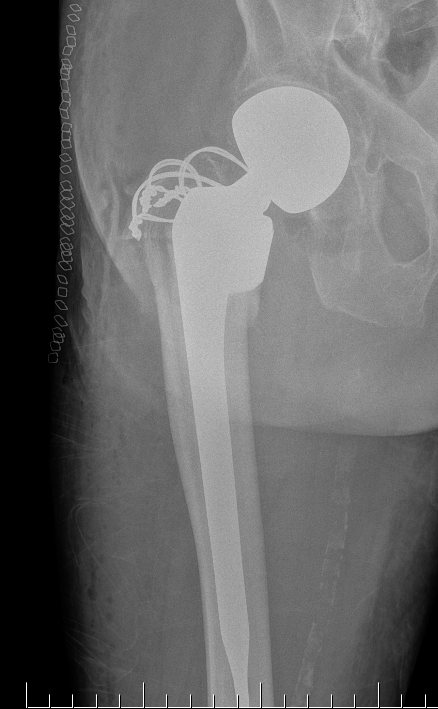

Hemiarthroplasty / Total hip replacement

Indications

- severe comminution

- salvage of failure of previous fixation

Technical

- may need calcar replacement

- may need greater trochanter fixation

D. Greater trochanter

- may need plate / cables to reduce